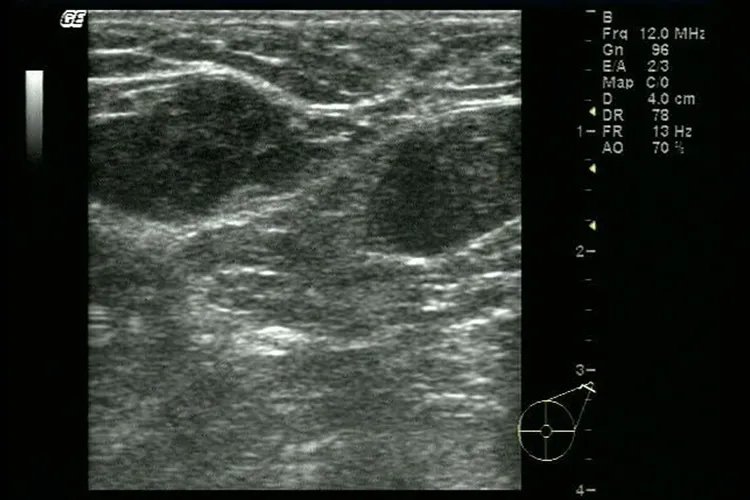

病因乳腺组织被位于皮下的浅筋膜所包绕,深浅筋膜之间由Cooper韧带相连。由于浅筋膜与皮肤相连,当乳腺癌侵及乳腺间的Cooper韧带使之缩短时,会牵拉皮肤,使局部皮肤凹陷,如同酒窝,称“酒窝征”。另外肿瘤直接与皮肤粘连也可能造成此种情况。治疗酒窝征的出现常提示乳腺癌存在的可能,一旦确诊要根据具体病情及时治疗。临床上常用的治疗方法有手术治疗、化学治疗、内分泌治疗、放射治疗、靶向治疗等。诊断乳腺癌酒窝征常根据乳房局部皮肤凹陷,如同酒窝这个典型特征进行诊断,同时可行体格检查,嘱患者上下活动患侧手臂,以便更准确的诊断。病史、体格检查以及乳腺超声、钼靶检查或MRI是临床诊断乳腺癌的重要依据。确诊乳腺癌,要通过组织活检进行病理检查。